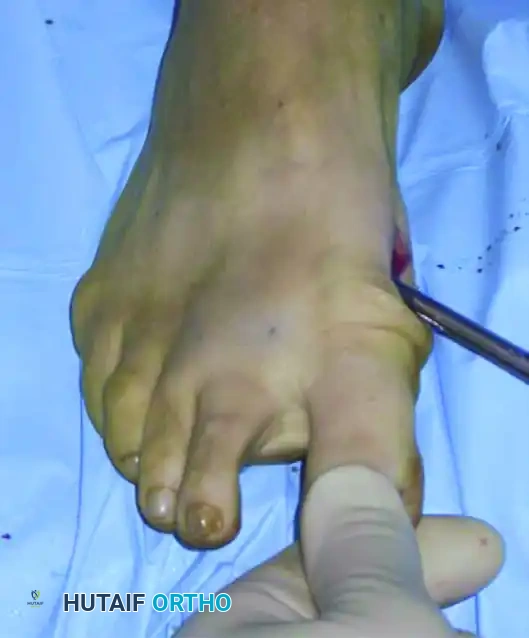

إدخال سلك التثبيت الدقيق

الخطوة الأولى تتمثل في وضع السلك المعدني الدقيق الذي سيقوم لاحقا بالتقاط وتثبيت رأس العظمة بعد قصها. يتم إدخال سلك بقطر ملليمترين بدءا من الزاوية الداخلية لظفر إصبع القدم الأكبر.

إدخال السلك المعدني الدقيق

يحرص الجراح بشدة على تجنب اختراق منبت الظفر لتفادي أي ألم أو تشوه في الظفر بعد الجراحة. يتم دفع السلك نحو الأعلى بحذر شديد. من الضروري جدا أن يمر السلك في مسار خارج غشاء العظم على طول الجانب الداخلي للإصبع. هذا المسار الدقيق هو ما يسمح لاحقا بإزاحة العظم وتصحيح التشوه.

مسار السلك المعدني خارج غشاء العظم

يتم دفع السلك حتى يستقر بقوة في الجانب الداخلي لرأس عظمة المشط. هذا التثبيت المحكم ضروري لمنع العظمة من التحرك بعشوائية بعد قصها.